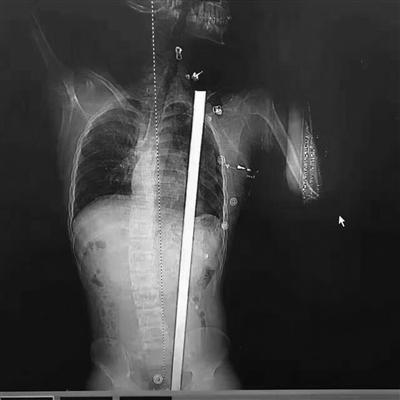

拍片显示患者体内的钢筋

“看到CT报告,我们发现钢筋直达肩胛”。徐进宇说,从报告上看,钢筋是从肛门旁进入,穿过腹部和胸部,所幸是从脾、胃、肾中间穿过,和心脏擦过,而且没有伤及大血管。徐主任说,小杨非常幸运,这根钢筋的走线都没有触碰到关键要害,如果伤到了致命血管,势必造成大出血,病人往往都等不及送医。